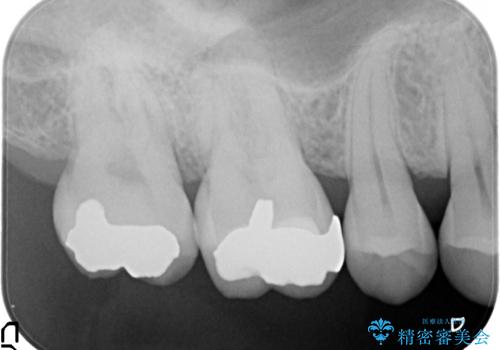

ゴールドインレーにて治療することとなりました。

ゴールドは目立つという点を除いては、非常に良い材料です。

奥歯の目立たない部位や、見た目をそこまで気にされない方にはお勧めです。